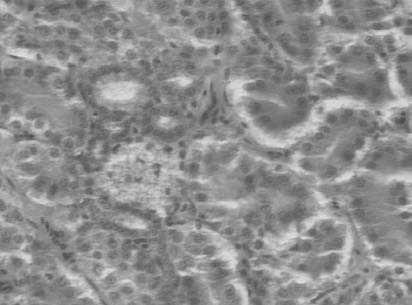

Figura 2. Imágenes histológicas características de cada grupo experimental: a) grupo A; b y c) grupo B; d) grupo C; e) grupo D; f) grupo E. CR: corpúsculo renal; fi: focos inflamatorios; flechas: grasa; barra en a, b, d, e, f: 30 mm; barra en c: 50 mm.

En el grupo A, grupo control o de individuos sanos, no se observaron depósitos de grasa, focos inflamatorios ni daño glomerular. Tampoco se observó fibrosis (fig. 2a).

En el grupo B, grupo control con dieta aterogénica, destacaban numerosas acumulaciones de grasa, que en muchas ocasiones ocupaban prácticamente todo el citoplasma en varias células contiguas, formando grandes acumulaciones grasas. En algunos cortes se observaban focos inflamatorios difusos rodeando las acumulaciones grasas. El mesangio de los glomérulos aparecía habitualmente denso y, en ocasiones, algunos casos obliterando la luz, características indicativas de daño glomerular (fig. 2b).

En el grupo C, grupo de regresión con dieta normal sin intervención con atorvastatina, se observaron numerosos depósitos grasos, aunque de menor tamaño y en menor cantidad. No eran destacables los focos inflamatorios. Los glomérulos presentaban un aumento del mesangio, aunque en menor cantidad que el grupo B. No se observaba fibrosis (fig. 2c).

En el grupo D, grupo de regresión con dieta normal e intervención administrando atorvastatina, las acumulaciones grasas prácticamente eran inexistentes y se asemejaban a las características del grupo control A. No se observaban focos inflamatorios. No destacaba daño glomerular ni fibrosis (fig. 2d).

En el grupo E, grupo de progresión con dieta aterogénica e intervención con atorvastatina, se describieron también grandes acumulaciones grasas y pequeños depósitos intracelulares aislados. Se observaron pequeños focos inflamatorios, daño glomerular moderado y no destacó fibrosis (fig. 2e).